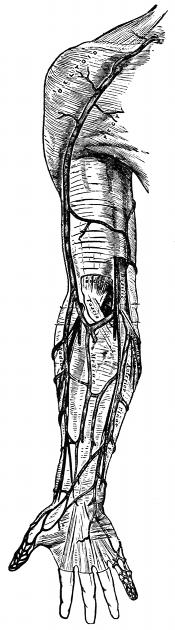

Fig. 4—Lymphatics of

the leg.